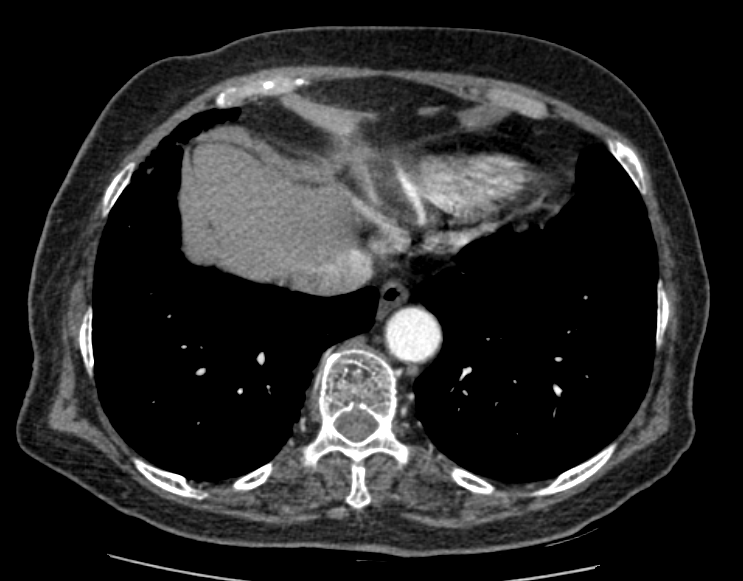

< Chest CT >